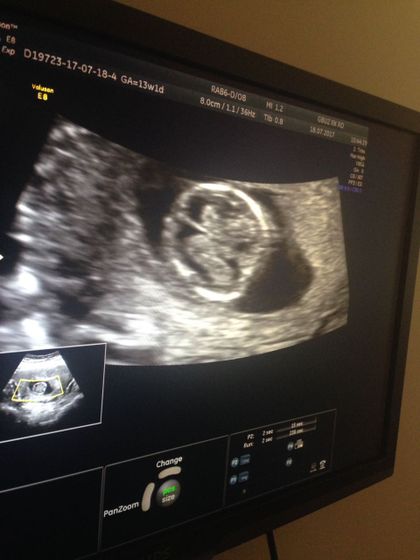

Итак! Все прошло отлично.Вчера очень волновалась, что мужа не пустят на узи)Но Урра! Пустили.С лялечкой все впорядке! Муж расстерялся когда увидел на мониторах настоящего человека с руками, ногами и т.д.Говорит божечки он шевелится????.Стоял и судорожно фотографировал.Лялечка очень активная, сложно было поймать нормальное фото.И все же со спины удалось сфотать.Смотрели двумя датчиками снаружи и внутри.Мочевой пришлось набирать… Срок 13,1 неделя.Ктр 67,1.Чсс 156уд.м, толщина воротникового пространства 1,8.Носовая кость 2,3мм.Кровоток в венозном протоке pi-0,93. По анатомии эмбриона все Б/О.Локализация левая боковая.длинна шейки 40мм.Следом сдала кровь из венки все отлично.Перед узи заставили покушать плотно.На кровь не влияет))Девочки кто разбирается по данным кости носа, не сильно большой?))

Нормы носа смотрела 12-13 неделя от 2,0 до 4,6 вроде, у нас 2,0 малюська)) а воротниковое пространство меньше 3. И я вас поздравляю))тоже вчера проходила, но у нас папу не пускают, следующий платно будем проходить, там и посмотрит

Я подумала по фото двойня

Нет это мозг)))))))